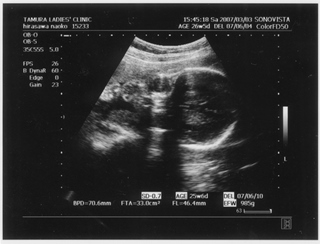

5ヶ月(18週と5日) 体重:262g BPD(頭を上から見た耳から耳の幅のような感じ):46.8㎜ FTA(お腹の断面):15.9平方㎝ FL(大腿骨長 太ももの骨の長さ):22.7㎜ 6ヶ月(22週と5日) 体重:602g BPD(児頭大横径 頭を上から見た耳から耳の幅のような感じ):57.6㎜ FTA(体幹横断面 お腹の断面):26.6平方㎝ FL(大腿骨長 太ももの骨の長さ):38.1㎜ まだこの頃は顔と上半身が収まっていました。 検診は妊娠23週までは、4週に一度なのでドキドキとワクワクです。 ちゃんと成長してるかなあなんて考えて行って、 心音をきいたり、エコーを見て毎回安心と喜びがわいてきます(*^_^*) たった4週で、体重は3倍近くにも!かわいいなあ☆ 6ヶ月の検診日ダンナっちは仕事だったから、 エコー写真を携帯で撮って送ると、 『目ん玉でてない!?』 と返事が返ってきました。 眼球がそう見えるんだろうけど、目のとても細いダンナっちには 衝撃的だったんですね(^。^;) 胎動を初めて感じた日をわたしはわかりません・・・ メモにとるなり、日記にかくなりすることをすっかり忘れてしまって、 今となって後悔<<o(>_<)o>> ダメな母親めっ と思いつつも、わたしらしいと感じ笑っています(^_^;) 12月の末に友達に、 「腸の動きか!?って思うのはあるんだけどまだよくわかんない」 と言ったのを覚えているので、12月の終わりから1月にかけての あたりなんでしょうね。 いつの間にかポッコポッコしていました! ベイビーこんなママだけどよろしく└|∵|┐♪┌|∵|┘ 6ヶ月までは、普通にそれまで履いていたジーンズも入っていたんだけど、 6ヶ月終わるころには、急に入らなくなってビックリしました~ 食生活の変化も特になかったです。 あ、ポテトチップスあまり自分で 買わなかったのに、1週間くらいブームの時期がありました!妊娠による影響かな!? 今、ベイビーはしゃっくりをしているみたいです |